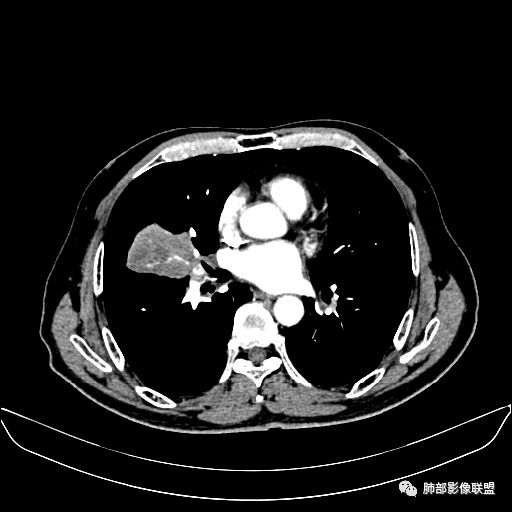

入院CT

老年男性,因“咳嗽咳痰1月余。”入院。病程中咳嗽咳痰,咳黄白痰,间断咯少许鲜红色痰血。PPD阳性。胸CT:右肺中叶外侧段支气管管腔阻塞,大片实性病变,病灶边缘光滑,部分边缘膨隆,可见分叶,肺门及纵隔可见肿大淋巴结,并可见钙化。增强可见病灶明显强化,而且延迟强化明显,病灶内多发低密度区,内见血管影,血管变细、部分血管破坏。考虑恶性病变可能性大,鉴别慢性肉芽肿性病变。

右肺中叶外侧段管腔阻塞、实性病变,病灶边缘光滑,可见分叶,肺门及纵隔可见肿大淋巴结,并可见钙化。增强可见病灶内多发低密度区。

老年男性,咳嗽、咳痰1月余,间断血痰。PPD阳性。

胸CT:跨叶大肿块,主体在中叶,右中叶外侧段支气管阻塞,病灶部分边缘膨隆,可见分叶,部分边缘平直,肺门及纵隔可见肿大淋巴结。增强病灶不均匀强化,延迟强化明显,病灶内多发低密度区,内见血管飘浮,部分血管变细、模糊。考虑:恶性病变可能性大,大细胞?淋巴瘤?鉴别慢性肉芽肿性病变。